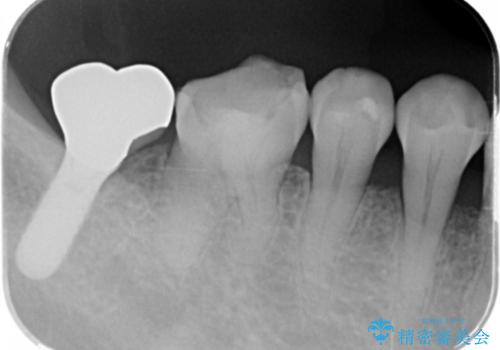

- 昔つめた材料が欠けたこと、歯の捻転を主訴に来院されました。

矯正治療の希望はなかったため、被せ物で歯の形を修正することになりました。

不適合だった詰め物の裏側に大きな虫歯がありました。

セラミックインレーやアンレーでは強度に不安が残るため、クラウンでの修復処置としました。

クラウンでは歯のがたつきを修正することもできます。

虫歯の除去と歯の捻転の両方を解決することができました。